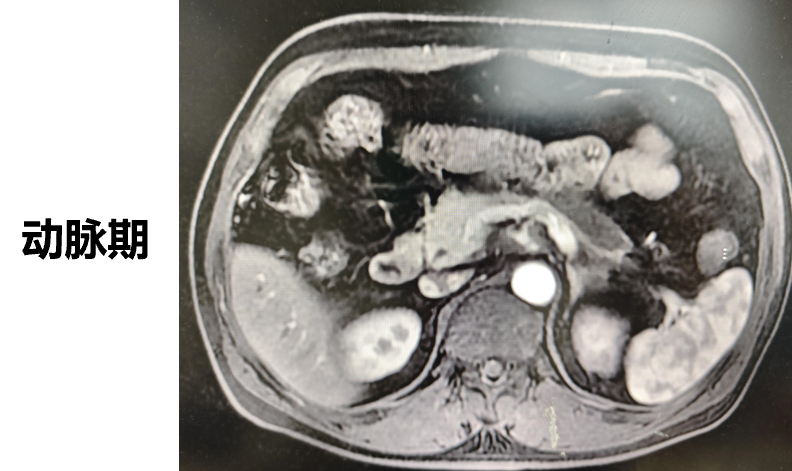

◈ 2022-7-19腹部MR增强扫描:提示T2WI及DWI胰腺体尾部信号稍高并胰管局限性稍扩张,肠系膜上动脉、腹腔干近段局部管壁增厚,需鉴别免疫相关性疾病累及或其他。

2022-7-19 上腹部MR增强扫描